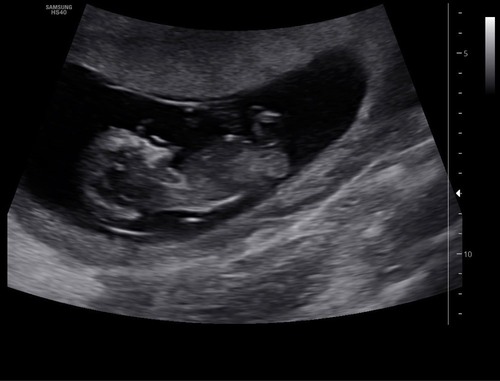

Enig idee wat het geslacht is? :) 10 weken + 6 dagen!